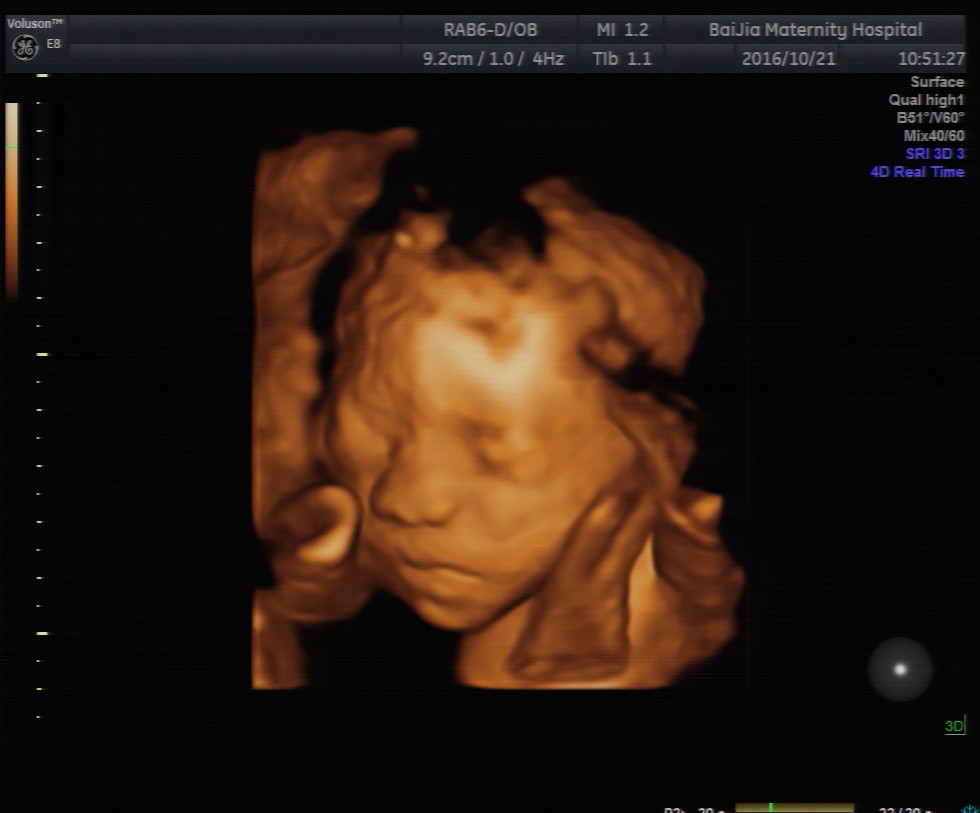

第一种:四维彩超是利用超声仪器中的软件将二维的平面图像模拟转换成动态、立体四维图像,有利于医生判断宝宝的发育情况是否正常以及是否存在重大畸形。检查时胎宝胎动比较频繁、表情动作也较多,像打哈欠、吸吮手指、吞咽口水等等,这些画面通过超声仪器呈现出来可能并不是那么好看。

第二种:胎宝宝的成长需要依附胎盘,所以面部可能紧贴着胎盘或者子宫壁引起变形,因此,在四维彩超成像时,宝宝的面部往往模糊不清,或某一部分直接变形,感觉比较丑。

第三种:四维彩超最佳检查时间段是孕20—24周,这个时期胎宝宝的各个器官刚刚发育完全,面部并不丰满,而四维彩超的成像是个放大的过程,所以可能出现大嘴、大鼻子、大脑门的外貌,看起来丑丑的。